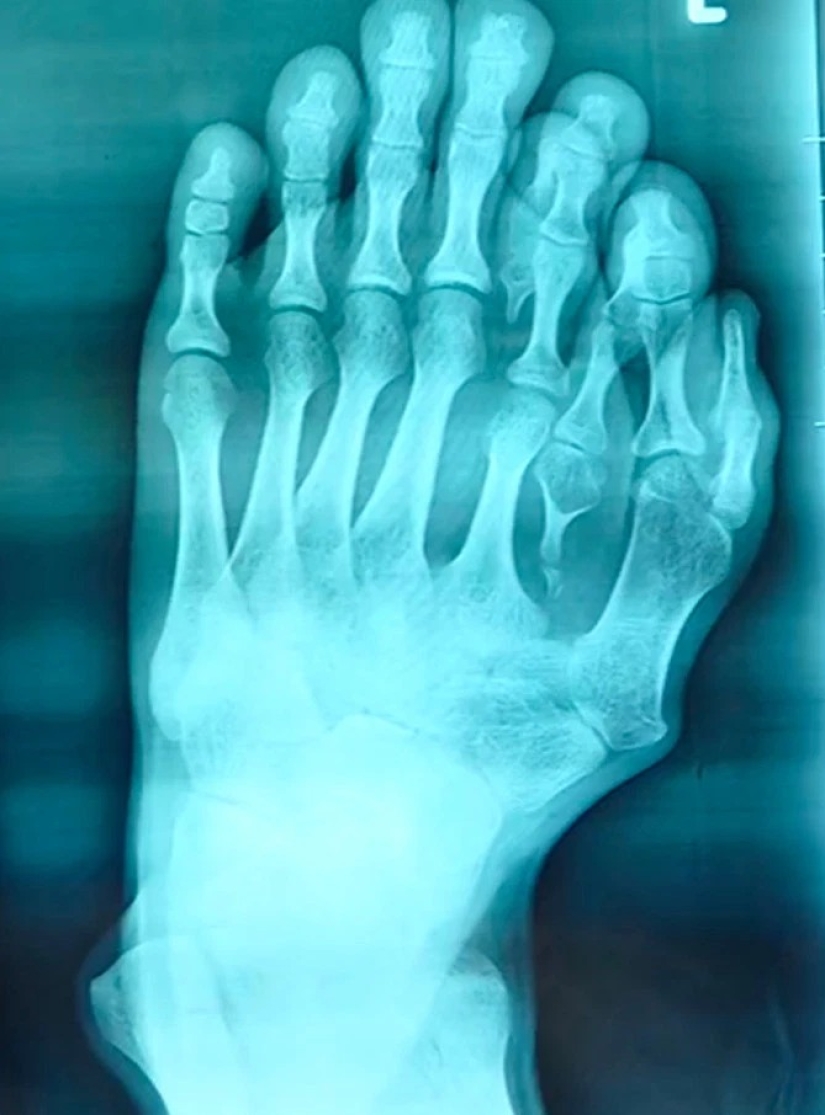

By Pictolic https://mail.pictolic.com/article/happiness-is-never-too-much-the-chinese-have-long-lived-with-14-toes-considering-the-anomaly-of-happy-sign.htmlThe man who was born with four extra fingers on the left leg, and thought about surgery to get rid of them, because his parents believed this anomaly sign of good luck. Only recently, 21-year-old Chinese man was operated on, giving the ability to wear shoes and to find happiness in his personal life. Find out how the guy lived with a rare deviation from our article.

The parents of 21-year-old Chinese by the name of Azzun believed that four extra fingers on my left foot the son is a sign of good fortune. The young people anomaly brought a lot of inconvenience in daily life, as well as physical suffering: in ten years he stopped wearing sandals because of the bleeding wounds on his legs.

When Azzouni matured, he turned for advice to the surgeons in the hospital Surgical Shunde Heping Hospital of Foshan city. His doctor At Xiang (Xiang Wu) said that such operations are doing in in childhood, so the 21-year-old patient was a special case.

The doctor says that children who are born with such disabilities need to operate up to six years before they go to school. This is important for the psychological state of the child, and to accelerate the process of recovery and adaptation.The young man believes that his life will finally get better. He hopes to meet a girl that will be happy. The guy is very grateful to the surgeons for giving him the opportunity to be normal. Superstition parents almost destroyed the life of Assuna, but common sense prevailed, and now the guy has a chance for a better future.